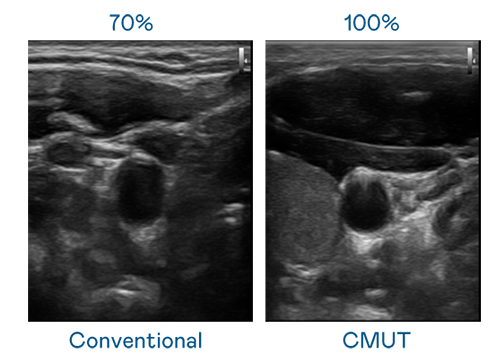

CMUT 技术是一种用电容式微机电元件来产生超音波讯号的技术。与传统 PZT 压电式技术相比,CMUT 频宽增加 30%,更宽频的超音波讯号让影像解析度大幅提升,是实现高影像品质医疗超音波扫描、促进精准医疗发展的关键技术。

大频宽带来超清晰影像

超音波影像的解析度高低,首先取决于探头能发出的讯号频宽。pp电子 CMUT 可提供高清晰的超音波讯号,提供高频宽、高灵敏度、影像纹理细节更高的超音波影像,协助医护人员缩短影像判读时间及利用精准的医疗影像进行诊断。